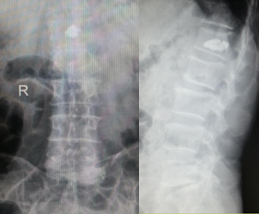

PKP技術(shù)(經(jīng)皮穿刺球囊擴(kuò)張椎體后凸成形術(shù))治療椎體壓縮骨折